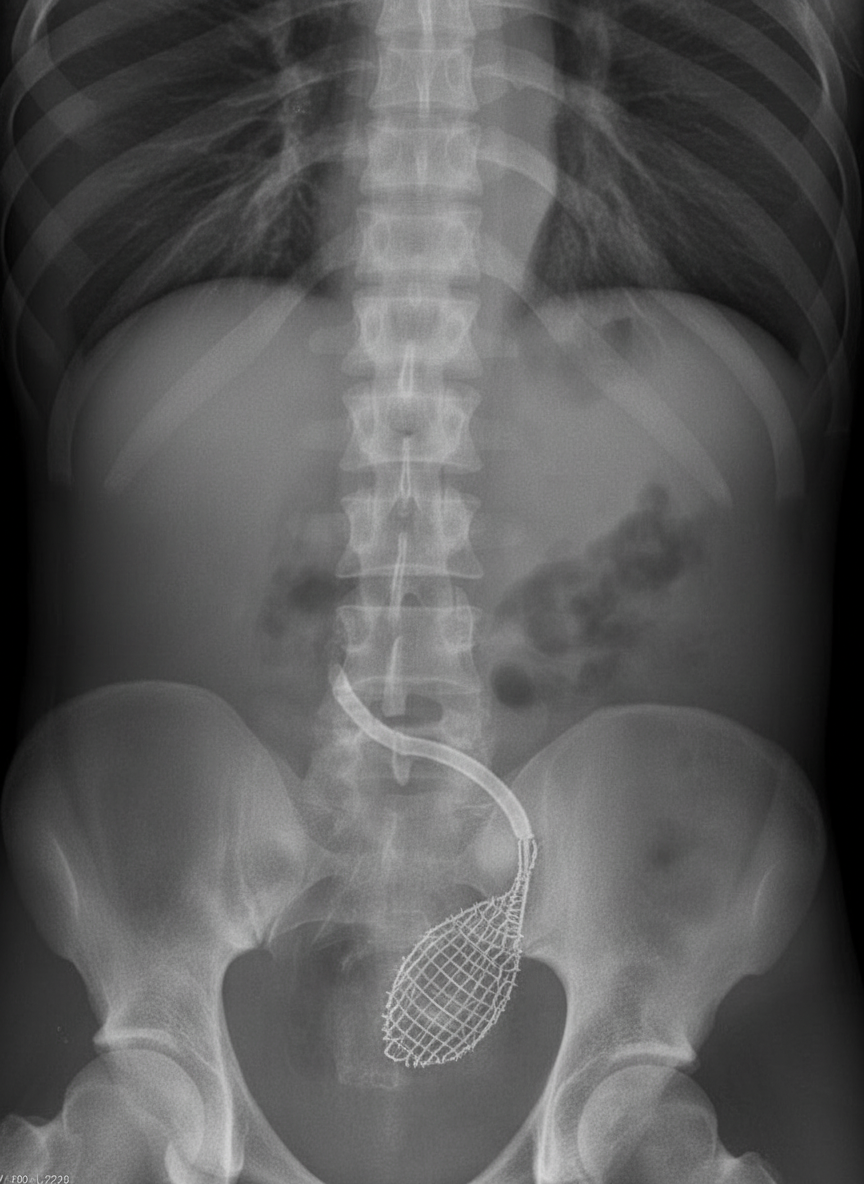

What procedure is shown in the ureter?

Explanation: ***Dormia Basket*** - A **Dormia basket** is a wire mesh device used for **stone retrieval** from the ureter, appearing as a characteristic **basket-like radiopaque structure** on fluoroscopy. - The basket is deployed beyond the stone, then **withdrawn** to capture and extract the calculus under direct visualization. *Stenting* - **Ureteric stents** appear as **straight radiopaque tubes** extending from the renal pelvis to the bladder, not basket-shaped structures. - Used for **drainage** and **relief of obstruction** rather than stone extraction procedures. *Dilatation* - **Ureteric dilatation** involves **balloon catheters** that appear as **smooth, elongated structures** when inflated, not wire mesh patterns. - Used to **widen strictures** or **prepare the ureter** for other procedures, not for stone retrieval. *Cannulation* - **Ureteric cannulation** involves **thin catheters** appearing as **fine radiopaque lines** within the ureter. - Used for **contrast injection** during **retrograde pyelography** or **guidewire placement**, not stone extraction.